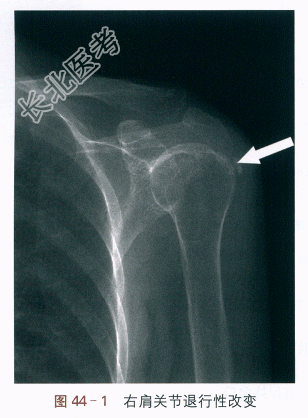

X线提示:右肩关节退行性改变,如图44-1所示。MRI提示:右肩关节腋隐窝处关节囊增厚并水肿,如图44-2所示。